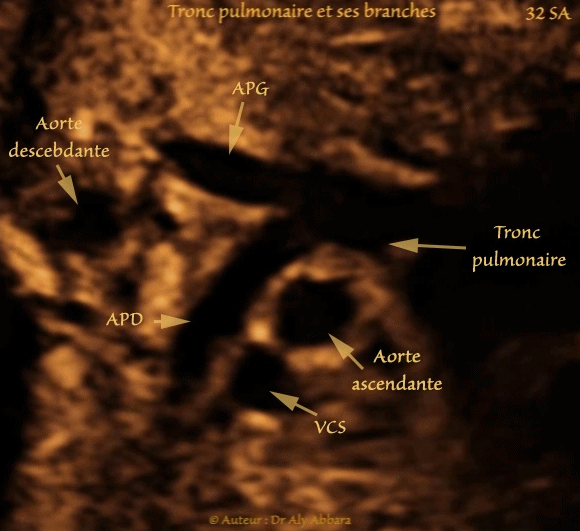

• Cœur fœtal à 32 SA : coupe du tronc pulmonaire et ses branches

• Cette image est l'illustration parfaite de la description anatomique suivante :

• Au-dessous de la crosse de l'aorte le tronc pulmonaire se divise en artères pulmonaires droite et gauche et en canal artériel.

• L'artère pulmonaire droite (APD) est plus longue et plus large que l'artère pulmonaire gauche ; elle chemine vers la droite horizontalement derrière l'aorte ascendante " Croisement de l'aorte et l'artère pulmonaire droite " et derrière de la veine cave supérieure avant d'atteindre le hile du poumon droit.

• L'artère pulmonaire gauche (APG) chemine horizontalement vers la gauche, à l'avant de l'aorte descendante.